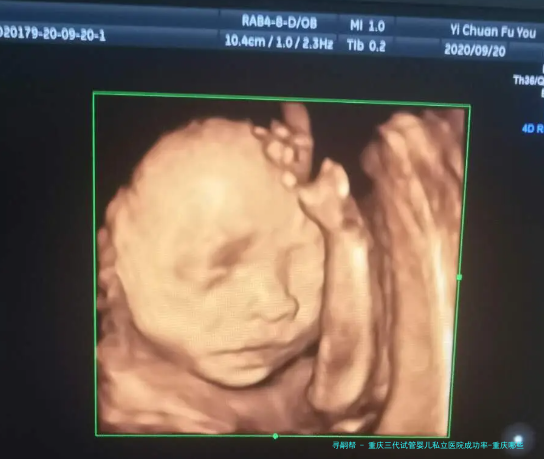

试管婴儿技术已然成为许多不孕夫妇实现生育心愿的有效途径。重庆作为国内西南地区的中心城市,拥有许多的医疗资金,其中私立医院在试管婴儿范围也取得了显着的成就。本文将关键要点推荐重庆三代试管婴儿私立医院的成功率以及相关信息。

自从1978年英国首次成功诞生了一名试管婴儿此后,这项技术得到了世界上的普遍应用和发展。而于国内重庆人民医院一直处于该范畴的先行者地位。该医院具有一支由国内外有名气权威人士构成的团队,在三代试管技术方面累积了丰厚经验,并取得了卓越的成功率。

通过对此医院过去五个年头实施的三代试管项目进行统计数据解析,我们可以看到其成功率远高于全国平均水平。在该医院实施的三代试管婴儿项目中,成功率达到了75%之上,大大超出国内其他私立医院。这一成绩受益于医院引进了最先进设备和技术,并严格按照国际规范进行操作。